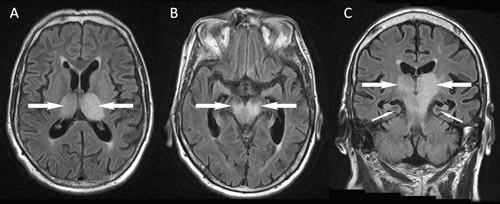

Magnetic resonance imaging (MRI) of the brain on Day 9 of symptoms showed confluent high signal bilaterally in the thalami, brainstem and the left precentral gyrus (Box 1). There was no evidence of ischaemic stroke, and findings on magnetic resonance angiography were unremarkable. Flavivirus-group and MVEV-specific reverse transcription polymerase chain reaction (PCR) findings were negative on CSF (Day 5, CSF diluted 1:2 because of the small volume available), and on plasma (Day 8). PCRs on CSF for alphavirus and herpes virus (types 1 and 2, Epstein–Barr virus and cytomegalovirus) were also negative. Flavivirus IgG was detected in serum by immunofluorescence (IF) on Day 4 at a titre of 1:640, but IF for flavivirus IgM and an MVEV-specific epitope-blocking enzyme-linked immunosorbent assay (ELISA) were negative. A Day 8 serum sample tested at another reference laboratory by epitope-blocking ELISA (targeting a different antigenic region11) showed MVEV-specific antibodies at a titre of > 1: 320, and was confirmed by a test for MVEV-specific neutralising antibodies. The results of IF for MVEV IgM remained negative. Other investigations did not show an alternative diagnosis. Unfortunately, the patient showed no clinical improvement and brain death was pronounced on Day 10. Treatment was withdrawn and an autopsy request was declined.

Radiological imaging makes a critical contribution to an early diagnosis of MVEV infection, often providing supportive information before serological results are available and helping to exclude alternative diagnoses. MRI is the most sensitive and specific type of imaging, and may show positive findings within a week of symptom onset. Typical features include bilateral hyperintensity of the deep grey matter, especially the thalami, on fluid attenuation inversion recovery or T2-weighted images (Box 1). These changes may also involve the temporal lobes, red nucleus and cervical spinal cord, and, in some cases, they may resemble those seen in HSV encephalitis.20 Findings may be similar for other flaviviruses, especially JEV and WNV, and thus MRI does not allow discrimination between these infections.20-24 Future studies are planned to determine if MRI can be used to predict patient outcomes. Unfortunately, MRI is not available in many rural areas and computed tomography (CT), which is more widely available, lacks the sensitivity to detect mild changes. In severe disease, CT may detect hydrocephalus, reduced attenuation from the thalami to the brainstem, cerebral atrophy or cerebral infarcts.16,25

1 Fluid attenuation inversion recovery magnetic resonance imaging of the brain of a 69-year-old man from flood-affected regional Victoria